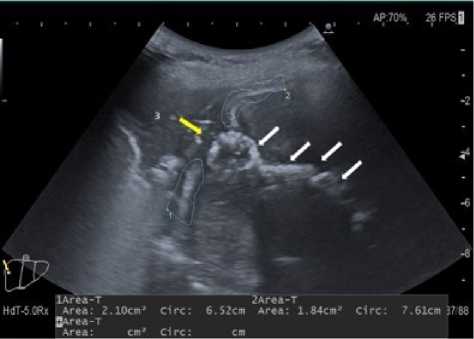

По результатам проведённого УЗИ органов брюшной полости (конвексным датчиком) в правом подпечёночном пространстве визуализировано гиперэхогенное образование с эффектом массивной акустической тени. Описанное образование линейной формы, с неровным контуром протяжённостью до 80 мм, в каудальной части образование с округлыми (кольцевидными) контурами. В краниальном отделе образование тесно прилежит к диафрагме (рис. 1, 2). Правый купол диафрагмы локально утолщён от 17 до 24 мм, контур диафрагмы на участке до 15 мм прослежен нечётко. В правой плевральной полости на фоне гиповентиляции лёгочной ткани и инфильтративных изменений купола диафрагмы определено отграниченное жидкостное скопление с неоднородным содержимым, размерами до 38×40×45 мм. Желчный пузырь удалён. Стенки холедоха не утолщены, конкрементов нет, просвет – 4 мм.

Рисунок 1. Ультразвуковое исследование в В-режиме. Линейная гиперэхогенная структура в правом подпеченочном пространстве с эффектом массивной акустической тени (отмечено белыми стрелками)

Figure 1. B-mode ultrasound. Linear hyperechoic structure in the right subhepatic space with the effect of a massive acoustic shadow (marked with white arrows)

Рисунок 2. Ультразвуковое исследование в В-режиме: 1, 2 – утолщенная диафрагма в области реберно-диафрагмального синуса; 3 – правая плевральная полость. Дефект диафрагмы (отмечено желтой стрелкой). Линейная гиперэхогенная структура в правом подпеченочном пространстве с эффектом массивной акустической тени (отмечено белыми стрелками)

Figure 2. B-mode ultrasound: 1, 2 – thickened diaphragm in the area of the costophrenic sinus; 3 – right pleural cavity. Diaphragm defect 1(marked with a yellow arrow). Linear hyperechoic structure in the right subhepatic space with the effect of a massive acoustic shadow (marced with white arrows)